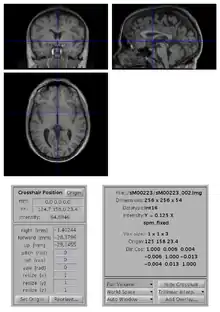

How to manually change the orientation of an image?

To change the origin of an image:

- open the image with SPM Display

- move the crosshair position so that it roughly points to the anterior commissure (AC).

- click on the Set Origin button

- click on the Reorient button and press done (your image is already selected). If you want to apply the same transformation to other images (e.g. if you have a series of functional images), select them all at this stage.

- say No to Do you want to save the reorientation matrix?

This will set the origin of the image (0 0 0 mm coordinates) to AC. You might also want to rotate the image such that it is better aligned with MNI space: to do so, you also need to edit the entries for the rotations (in radian) along the pitch, roll and yaw axes.